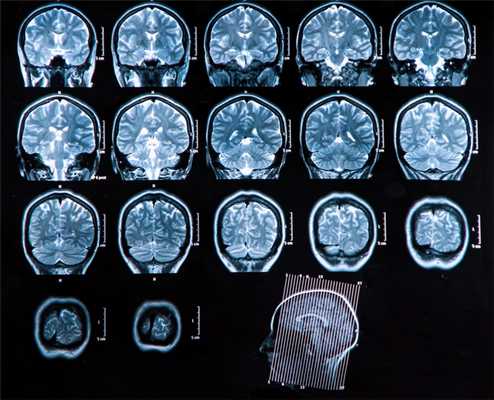

Основной метод оценки непосредственно вещества головного мозга (в том числе первичных опухолей и метастазов) — МРТ с применением контрастного усиления.

Вопросы стадирования (поиск отдаленных метастазов) лучше всего решаются с помощью ПЭТ, в том числе с метионином.

Компьютерная томография используется как дополнительный метод в случае, если требуется оценка состояния костных структур, а также при наличии абсолютных противопоказаний к МРТ исследованию (наличие металла в теле — например, кардиостимулятора, ферромагнитных инородных металлических соединений: пластины, протезы, импланты и т.п.)

Головной мозг